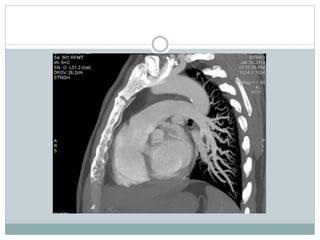

These two CT images show a large pulmonary embolus in the left main

branch of the pulmonary artery. On the left is a lateral view of the artery and

on the right is the anterior view of the same artery.